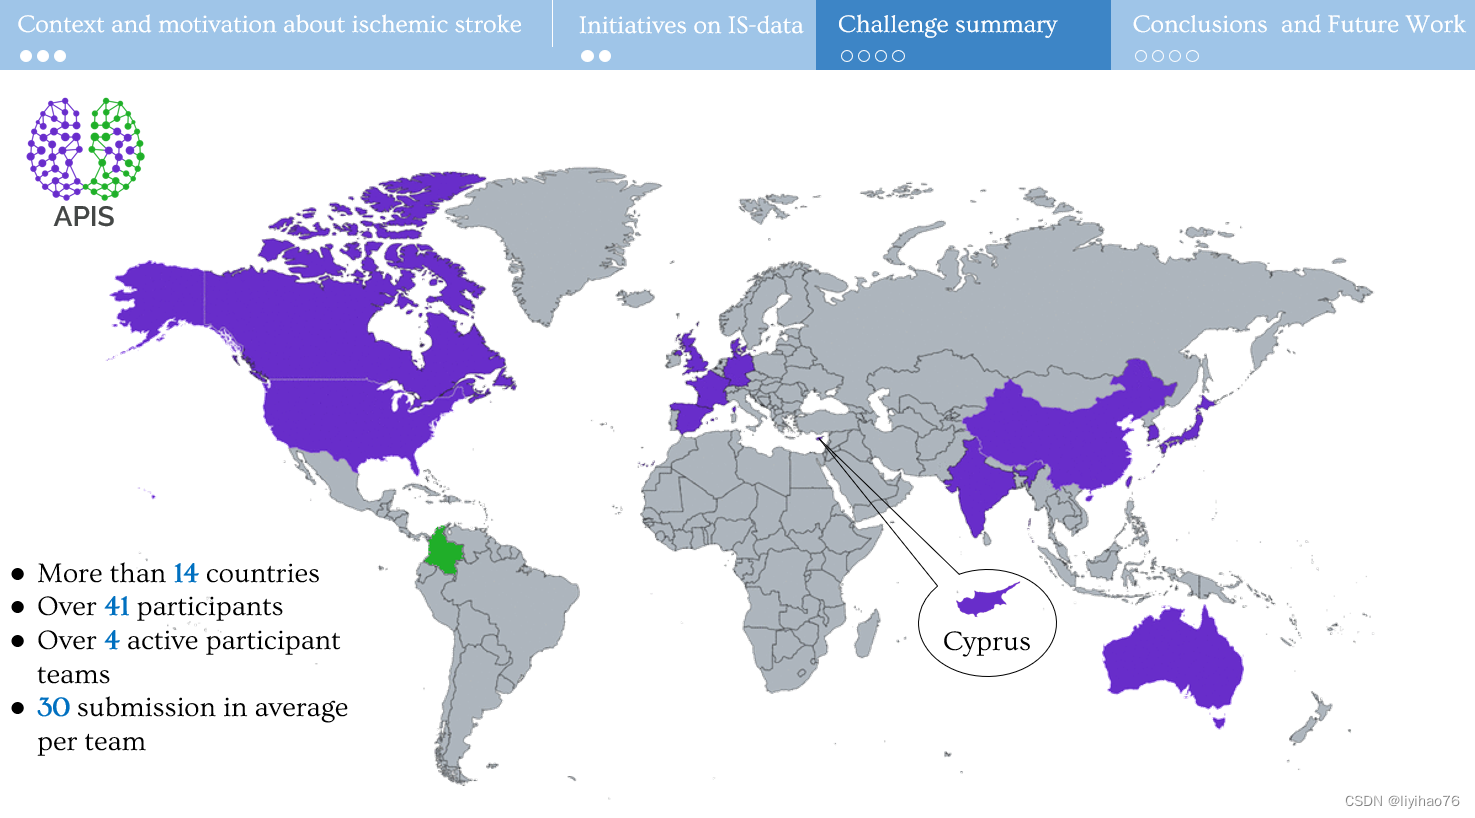

中风是全球第二大死亡原因。 即时诊断的关键组成部分是定位(通过 CT 扫描)和病变描绘(通过 MRI 研究)。 尽管如此,病灶的描绘仍然很差,仅在晚期可见,并且分析使用手动描绘。 这个挑战引入了 CT 和 ADC 研究的配对数据集。 邀请研究人员提出计算策略,在训练期间处理配对数据,并处理 CT 起始序列上的病变分割。 在培训期间,将提供带注释的配对序列(来自一位专家),并且将针对两位专家比较用于测试的结果分割。

CT (NCCT) 主要允许对中风和其他病理进行分类。 然而,此类序列对缺血的对比度差、敏感性和特异性低,并且病变的低衰减具有时间依赖性。因此,临床方案包括扩散加权 MRI 序列,例如 ADC(表观扩散系数),以正确描述和量化中风病变,除其他外,允许正确显示缺血半影和缺血核心。APIS 挑战赛提供配对 (CT-ADC) 数据集。 有 60 个成对的 (CT-ADC) 数据集以及来自专业放射科医师的相关描述以供训练。 最后将使用40个数据集作为测试集进行验证